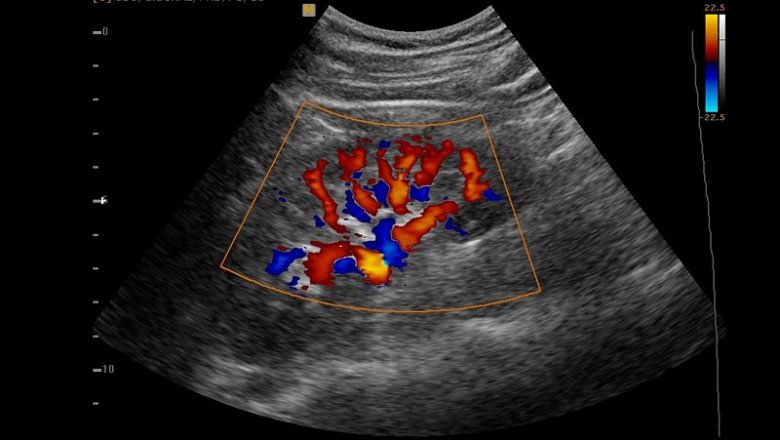

A Doppler Ultrasound Can Be Used To Assess Blood Flow In An Area

A Doppler Ultrasound is a test that measures the quantity of blood flow through your arteries and veins, often those that provide blood to your arms and legs. It uses high-frequency sound waves. Blood flow tests, sometimes referred to as vascular flow studies, are able to identify aberrant blood flow within an artery or blood vessel. Blood clots and impaired circulation are just two diseases that can be diagnosed and treated with this. A blood flow study may involve the use of a Doppler ultrasonography.

A Doppler Ultrasound is a quick, painless, and minimally invasive technique. The test gives your doctor crucial knowledge about the blood flow through your principal arteries and veins. Also, it can show places in the arteries that have restricted blood flow or are obstructed, which could eventually result in a stroke.